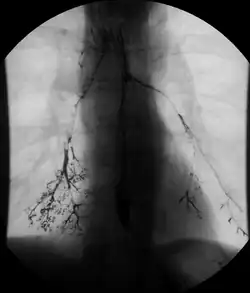

Normal barium swallow fluoroscopic image, showing the ingested barium sulfate being induced down the oesophagus by peristalsis. | |

An upper gastrointestinal series, also called a barium swallow, barium study, or barium meal, is a series of radiographs used to examine the gastrointestinal tract for abnormalities. A contrast medium, usually a radiocontrast agent such as barium sulfate mixed with water, is ingested or instilled into the gastrointestinal tract, and X-rays are used to create radiographs of the regions of interest. The barium enhances the visibility of the relevant parts of the gastrointestinal tract by coating the inside wall of the tract and appearing white on the film. This in combination with other plain radiographs allows for the imaging of parts of the upper gastrointestinal tract such as the pharynx, larynx, esophagus, stomach, and small intestine such that the inside wall lining, size, shape, contour, and patency are visible to the examiner. With fluoroscopy, it is also possible to visualize the functional movement of examined organs such as swallowing, peristalsis, or sphincter closure. Depending on the organs to be examined, barium radiographs can be classified into "barium swallow", "barium meal", "barium follow-through", and "enteroclysis" ("small bowel enema"). To further enhance the quality of images, air or gas is sometimes introduced into the gastrointestinal tract in addition to barium, and this procedure is called double-contrast imaging. In this case the gas is referred to as the negative contrast medium. Traditionally the images produced with barium contrast are made with plain-film radiography, but computed tomography is also used in combination with barium contrast, in which case the procedure is called "CT enterography".[1]